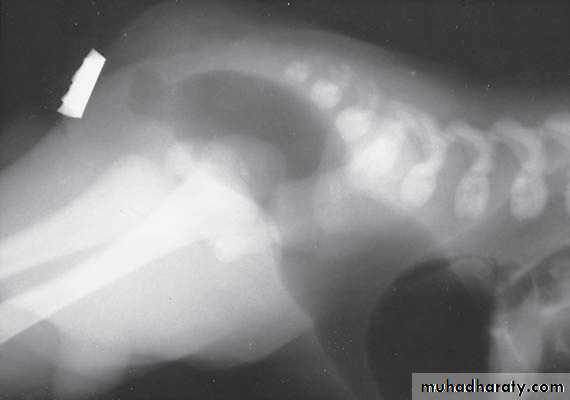

Oesophageal Atresia and Tracheo-Oesophageal Fistula,